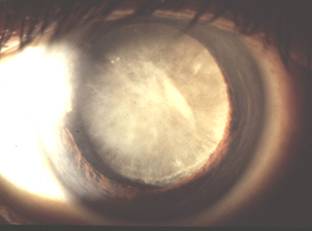

白內障

當眼球原本清晰透明的晶狀體變得渾濁而影響視力時,便稱為白內障。晶狀體的功能猶如相機的鏡頭,把光線準確地聚焦在視網膜上,當晶狀體變得渾濁,光線便無法完全透過,視力便會下降,視力質數也會受到影響。